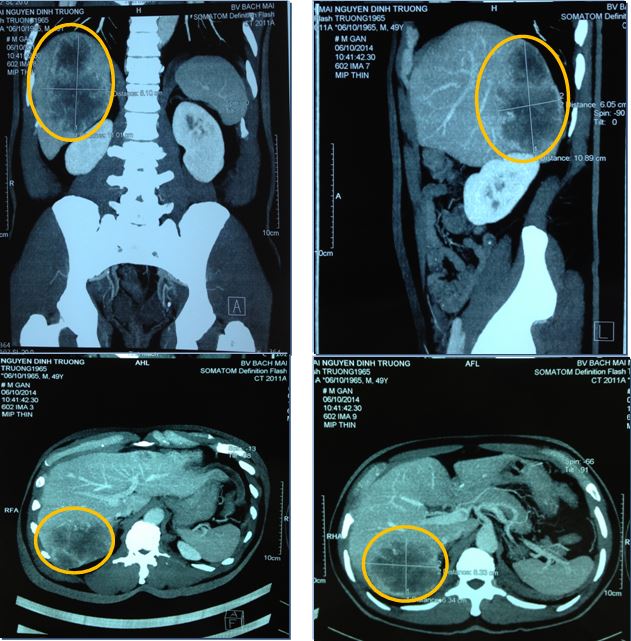

Chụp MSCT ổ bụng

Hình 1: Hình ảnh khối u hạ phân thuỳ 6 gan phải, kích thước 8,5 x7,2 cm, khối u gan trái 3,1 x2,1 cm

Hình 4: Hình ảnh khối u trước điều trị 7,0 x 8,6 cm (A) và sau điều trị 3,0 x 3,5cm (B)